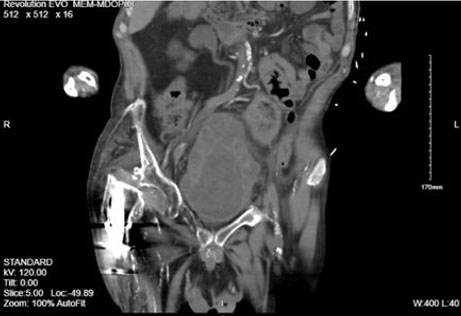

Repeat imaging two days later showed interval decompression of the bladder and the absence of discrete fluid collections within the bladder wall. Asymmetric bladder wall thickening was noted, indicative of bladder diverticuli, some of which had stones (Figure 2). The patient was eventually stabilized and discharged on Cefepime to complete a 14-day course to be dosed along with his home hemodialysis. Follow-up office flexible cystoscopy revealed multiple significant diverticula and numerous punctate bladder stones with no evidence of abscesses or tumors (Figure 3). Taking the cystoscopy and most recent CT findings into account the fluid collections seen within the bladder wall on original CT images were likely due to sediment and pus filling the bladder diverticula secondary to urinary retention from a poorly draining catheter.

Figure 2: Repeat CT scan done after 48 hours of bladder decompression with replaced catheter and antibiotics for UTI. Fluid collections around bladder that were seen on initial CT scan are no longer present, and instead, circumferential bladder diverticula are noted.